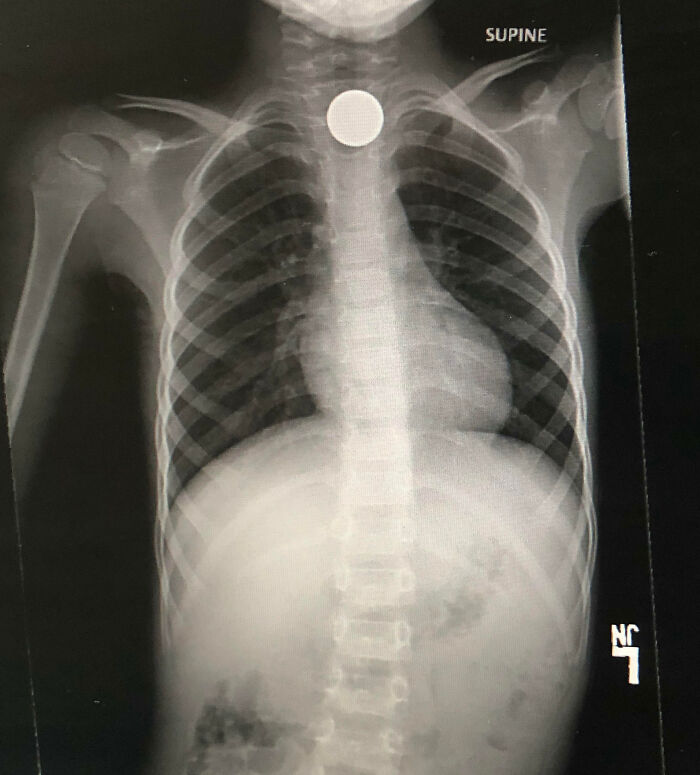

#7 Son Decided To Swallow A Nickel And Turn $.05 Into $4400.00

Image source: Kingsdontbeg